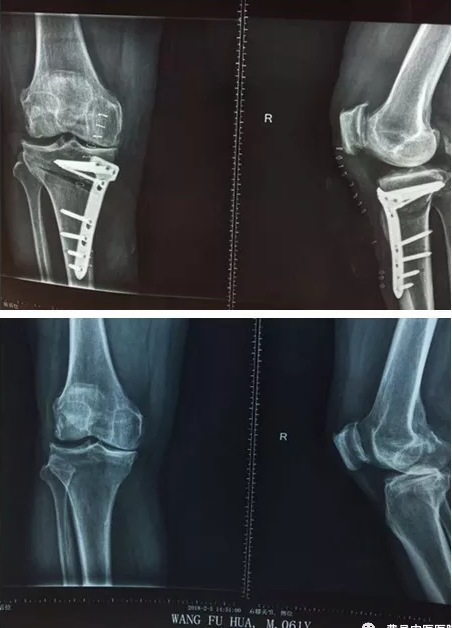

患者王XX、男、60歲,因右膝骨性關節炎緻右膝關節疼痛,嚴重影響正常生活。經多方求醫,均建議行“人工關節置換” 術,經骨二科主任郭士金診療,考慮到患者年齡尚可,關節置換會給患者帶來諸多不便,郭主任考慮采用最新微創矯形技術——HTO截骨術,保留病人膝關節,病人欣然接受,手術僅需5-6厘米小切口,手術時間不到1小時,術後12小時就能在助行器支撐下練習行走。

HTO截骨手術是一種保膝治療手術,無需置換入人工關節假體,手術風險低,創傷較全膝關節置換明顯降低,術後恢複快、減短住院日期和降低醫療費用,最主要是患者膝關節本體感覺存在,無異物感。